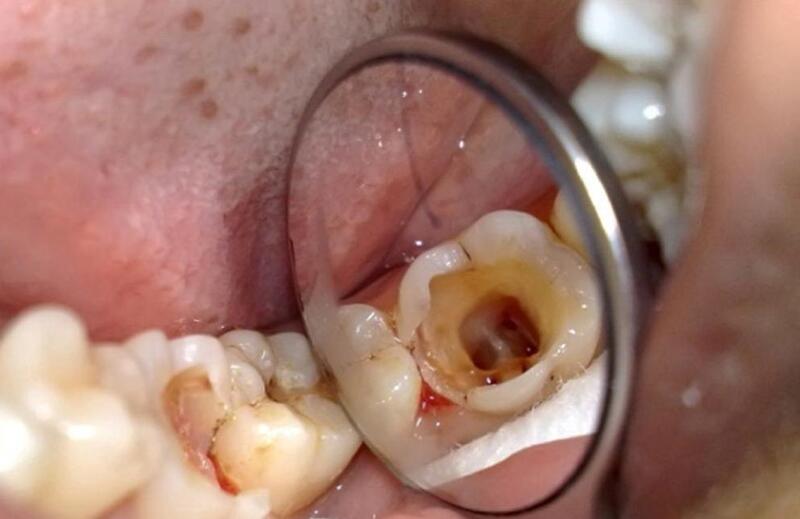

– Lỗ sâu ăn tới tủy răng nên gây đau nhức, có thể phát đau tự nhiên không cần tác động và thường đau nhiều hơn vào ban đêm.

– Viêm tủy cấp hoặc mãn tính, tủy hoại tử.

– Vùng nướu quanh răng bị sưng đỏ, có thể chảy mủ và gây mùi hôi khó chịu trong miệng.

– Áp xe quanh chóp răng hoặc u hạt quanh chóp.

– Răng đổi màu xám, đen do chết tủy.